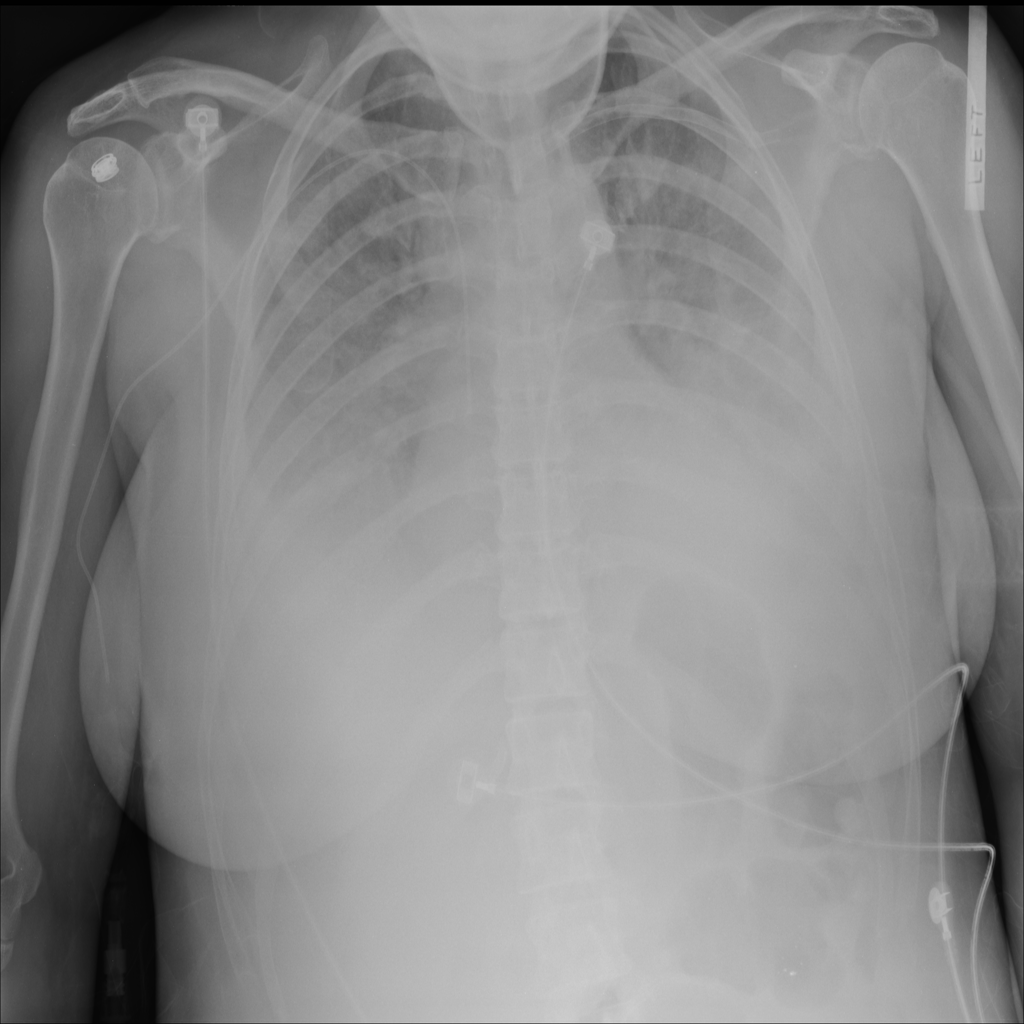

Consolidation

Consolidation refers to air-space filling that makes part of the lung appear denser on imaging.

Showing up to 90 reference images for Consolidation.

PAT-531A · IMG-006Consolidation

PAT-531A · IMG-006

PA